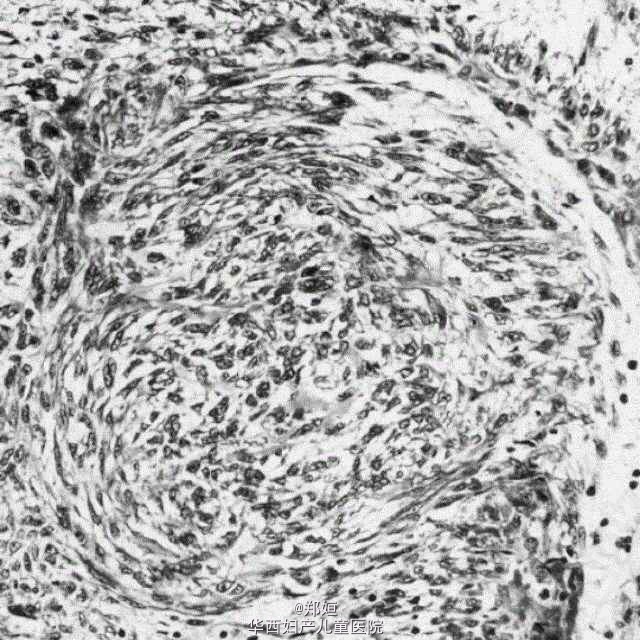

子宫血管周围上皮细胞肿瘤

32岁女性,G0P0,下腹和左腿疼痛11月余

MRI提示子宫底5cm浆膜下肿块。

行手术治疗,术中可见有弹性的子宫肿块,与左侧阔韧带相邻。 切除肿块,无其余异常。

预后良好 doi:10.1097/PGP.0000130448.30412.79